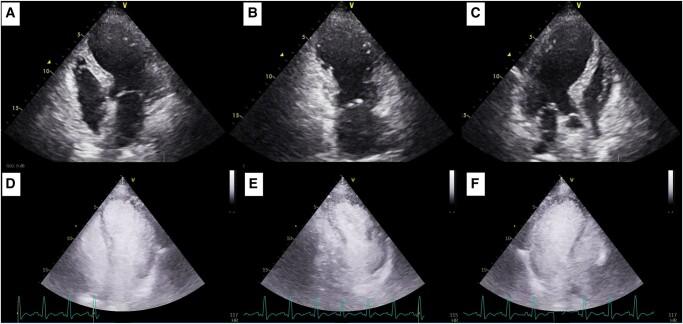

CASE SUMMARY

We describe a TTS case presented with cardiogenic shock due to ventricular septal rupture (VSR). Successful treatment involved mechanical circulatory support followed by VSR surgical closure.

我们描述了一例因室间隔破裂(VSR)导致心源性休克的TTS病例。成功的治疗包括机械循环支持,随后进行VSR手术闭合。